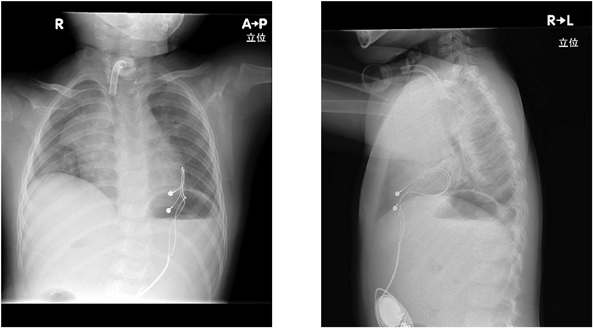

以上2回の意識消失エピソードはCCHSの自律神経の異常に伴う一過性徐脈による失神と考え,PMI適応と判断し,5歳2カ月時にPMI(VVI, Medtronic Azure XT SR MRI W2SR01)を施行された(Fig. 4).最低心拍数は60拍/分に設定し,以後,失神なく経過している.5歳6カ月(PMI施行後4カ月)時点でのペーシング頻度は1%未満で推移している(Fig. 5).

Pediatric Cardiology and Cardiac Surgery 42(1): 21-26 (2026)

Fig. 4 Chest X-ray after pacemaker implantation